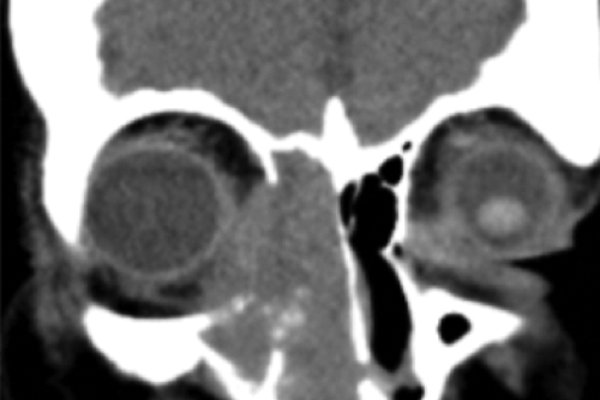

Chronic dacryocystitis?